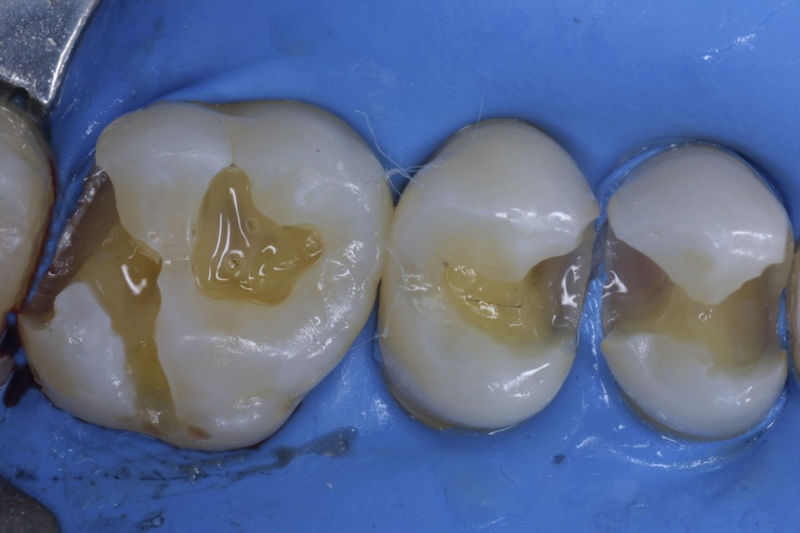

Restauraciones fabricadas en el laboratorio con materiales estéticos, los cuales cubren de manera parcial dientes posteriores. Se utilizan primariamente para restaurar dientes con caries, fracturas y/o defectos amplios. Para poder enviar el caso al laboratorio se toman impresiones utilizando materiales de impresión o técnicas modernas digitales.

Restauraciones fabricadas en el laboratorio con materiales estéticos, los cuales cubren de manera total dientes anteriores y posteriores. Se utilizan primariamente para restaurar dientes con caries, fracturas y/o defectos amplios, así como soportes de puentes. Para poder enviar el caso al laboratorio se toman impresiones utilizando materiales de impresión o técnicas modernas digitales.

Disciplina fundamental de la Odontología enfocada en el diagnóstico, prevención y tratamiento restaurador de las piezas dentales que han sufrido daños. Su objetivo principal es devolver al diente su equilibrio biológico, funcional y estético cuando su integridad ha sido alterada. Resinas directas, incrustaciones, coronas.